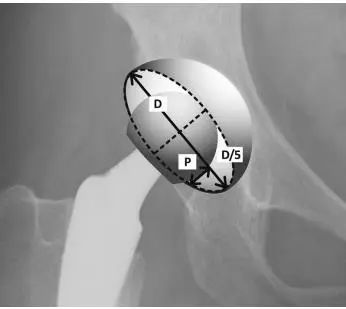

4.Pradhan’s method:D是臼杯椭圆长轴上的最大距离。绘制一条垂直于长轴并与构件边缘相交的直线,从纵向直线总距离的五分之一的点开始。P是沿这条垂直线从纵线到边缘的距离(图4)(anteversion = arcsin (P/0.4D)